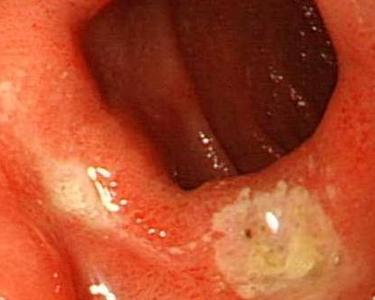

食道炎(又名食管炎)是指食管黏膜浅层或深层组织由于受到不正常的刺激,食管黏膜发生水肿和充血而引发的炎症。这些刺激有胃酸、十二指肠反呕上来的胆汁、烈酒、辣椒、太热的菜汤、过于浓热的茶等等。食道炎可分为原发性与继发性食道炎。食道发炎的原因有许多,像是严重呕吐后,长期放置鼻胃管或服用阿斯匹宁、强酸强碱、非类固醇类消炎药或接受化学治疗、放射治疗之患者或是病患本身抵抗力下降而受结核菌或念珠菌或病毒感染导致食道炎。食道炎的类型有放射性食道炎,表层脱落性食道炎,急性腐蚀性食道炎,化脓性食道炎。食道炎容易引起食道溃疡,食管狭窄,食道恶变,胃肠道出血。